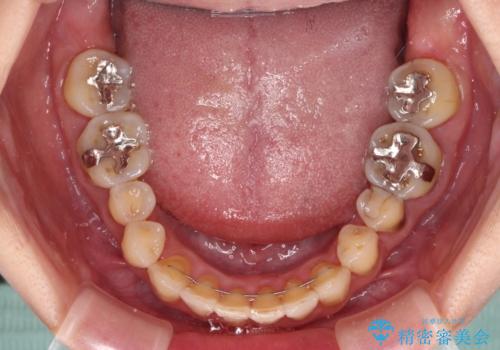

- 歯列不正と、どこで咬んで良いのか分からない咬み合わせを気にして来院された患者様です。

下顎骨は左側にシフトしており、咬み合ったときには奥歯と前歯の一部しか接触していない状態でした。

骨格的な左右差は歯列矯正は改善できないため、上下歯列が全体的に接触することをゴールとしてインビザラインにて矯正治療を行うこととしました。